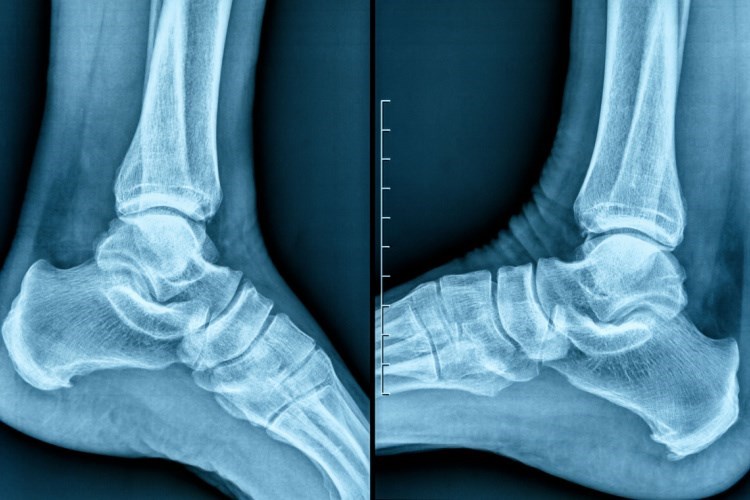

תיבדק מערכת העצבים של השרירים והשלד באזור הקרסול וכף הרגל כולל בדיקת רפלקסים, כוח שרירים, מתח שרירים, קואורדינציה, שיווי משקל והתחושה. בדיקות נוספות יכולות להיות צילום רנטגן, בדיקות דם או בדיקות דימות כמו אולטרסאונד או MRI.

צילום רנטגן של כף הרגל. אילוסטרציה: שאטרסטוק